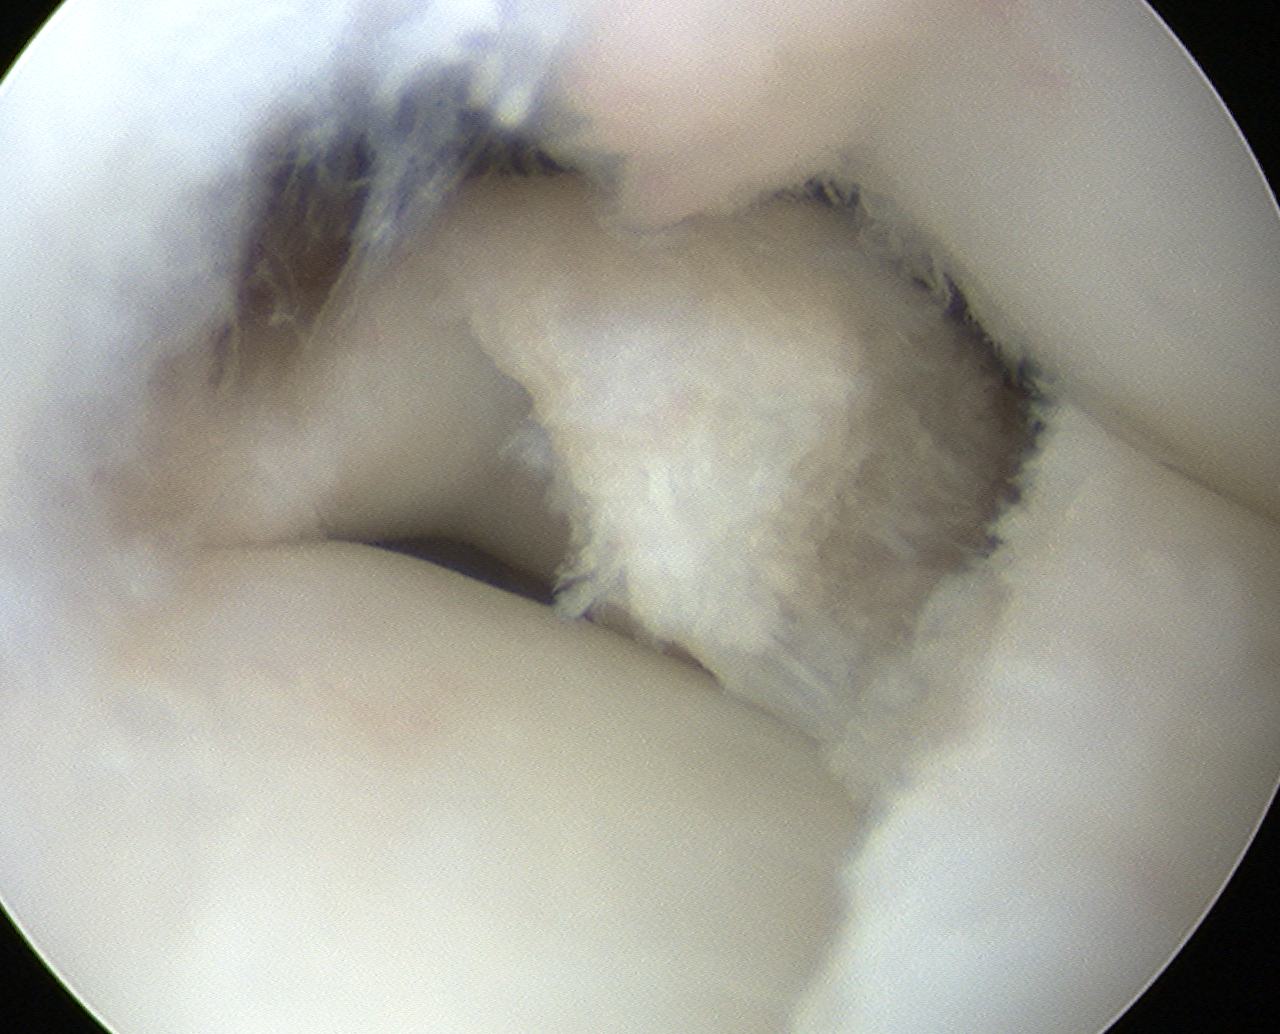

Classification Watanabe

1. Complete

- entire articular surface of tibial plateau covered by thickened abnormal meniscus

- minimal symptoms

- stable - i.e. capsular attachments intact

Technique Saucerisation

Technique

- make incision with scissors in medial aspect

- resect posterior part

- saucerise laterally and anteriorly

- need to ensure don't detach anterior horn